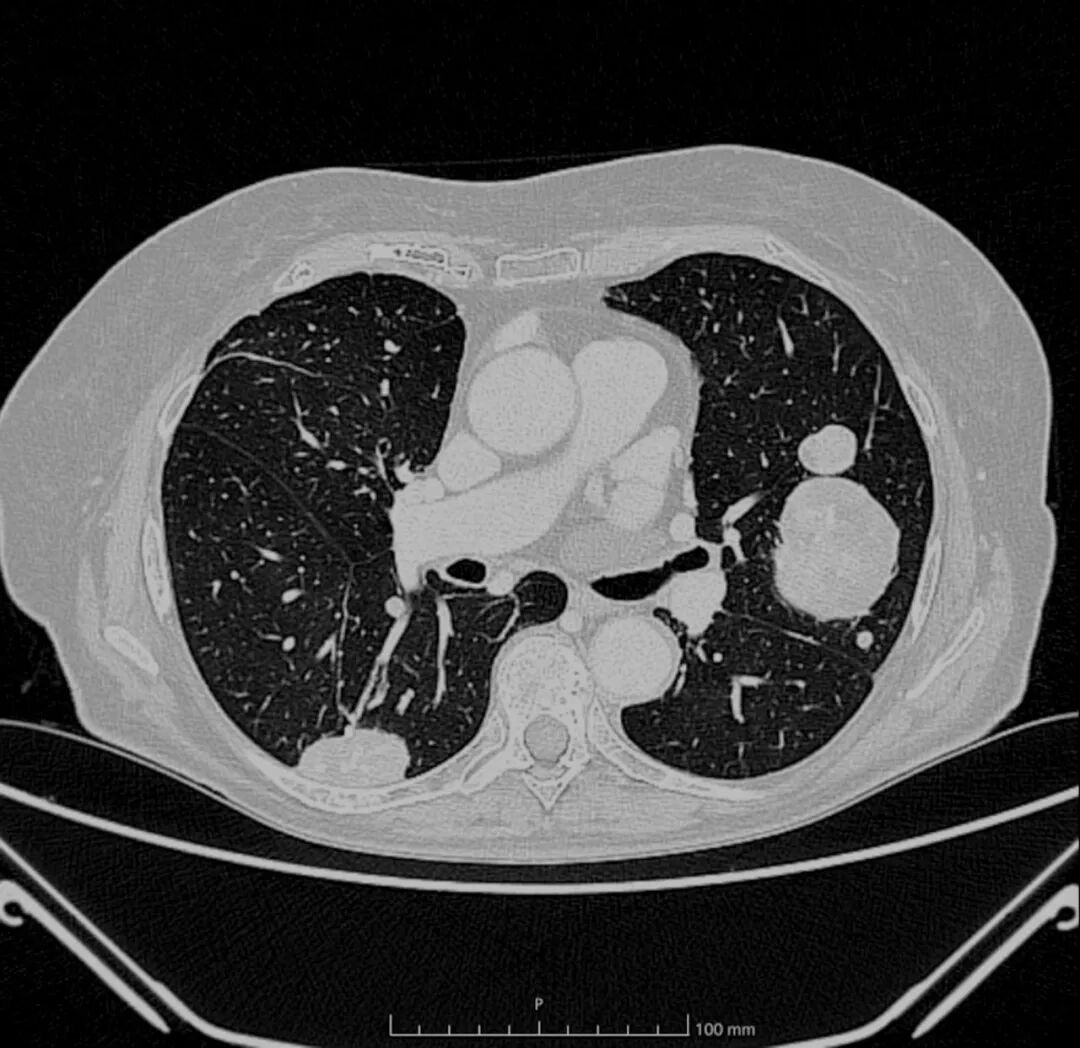

图2. 胸部CT扫描横断面显示双侧肺部平滑肌瘤,表现为大的肿块,周围肺组织正常。

全身CT扫描显示,与2023年CT扫描相比,双侧多发性肺部肿块大小进一步增加(左侧最大者7.2 cm对比6.2 cm),边缘清晰,内部可见粗糙的血管结构和坏死液化灶(图2)。未检测到额外结节。在奇异食管凹陷处报告的部分实心结节为实心圆润,测量为11毫米(对比9毫米)。证据显示右上肺叶和同侧下肺叶需进行楔形切除。检查未发现其他器官有其他病变。心脏磁共振显示室间隔中段基底部有一大肿块(最大尺寸,5×35cm)(图3A)。对比剂注射后序列显示不规则晚期钆增强,提示右心房存在一个通过细长蒂附着的肿块(最大尺寸,2.5×3cm)(图3B),该肿块在对比剂注射后序列中未见晚期钆增强。